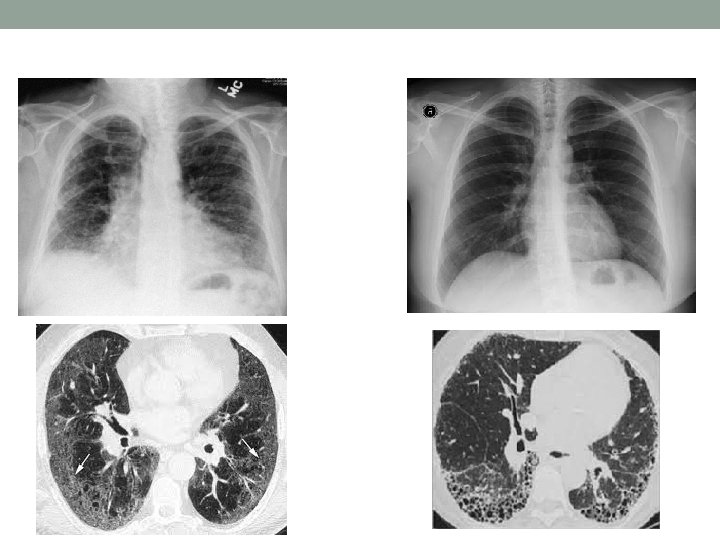

Interstitial Lung Disease

ILD • ILD: is defined as a specific form of chronic, progressive fibrosing interstitial pneumonia leading to progressive loss of pulmonary function, and respiratory failure. • Who should be screened for ILD: EVERYBODY • It affects usually the bases of the lungs. • Diagnosis is made by a combination of imaging and pulmonary function test (PFT).